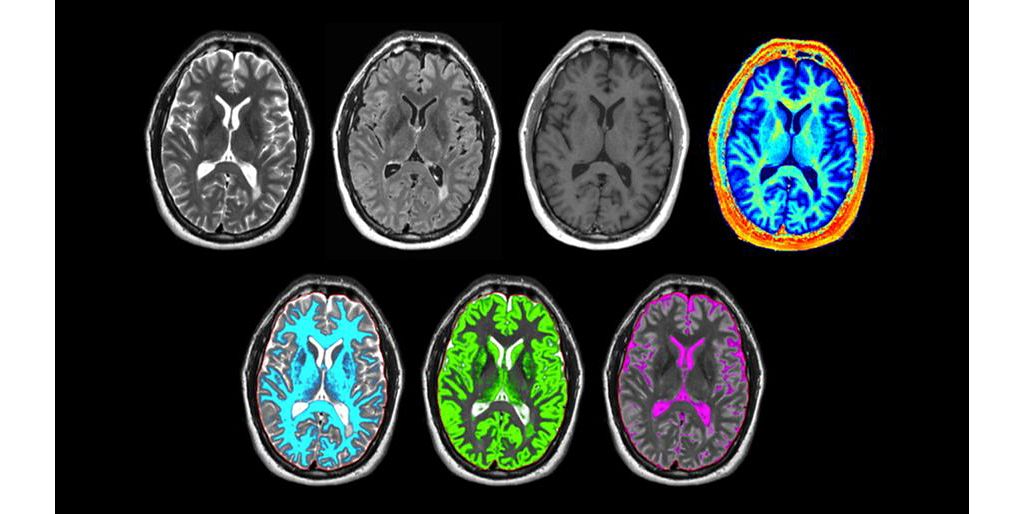

SyntAc allows you to perform MR imaging with a single quantification scan. The acquisition time can be decreased thanks to compatibility with Philips SmartSpeed and compatibility with Compressed SENSE acceleration technology. The resulting data can be used as input for advanced 3rd party processing software* to synthesize MR images with different contrasts, brain parenchyma fraction maps and/or brain segmentation maps

• Segmentation Grey matter (synthetic)

Segmentation Grey matter (synthetic)

• T2 map (synthetic)

T2 map (synthetic)

• T1w (synthetic)

T1w (synthetic)